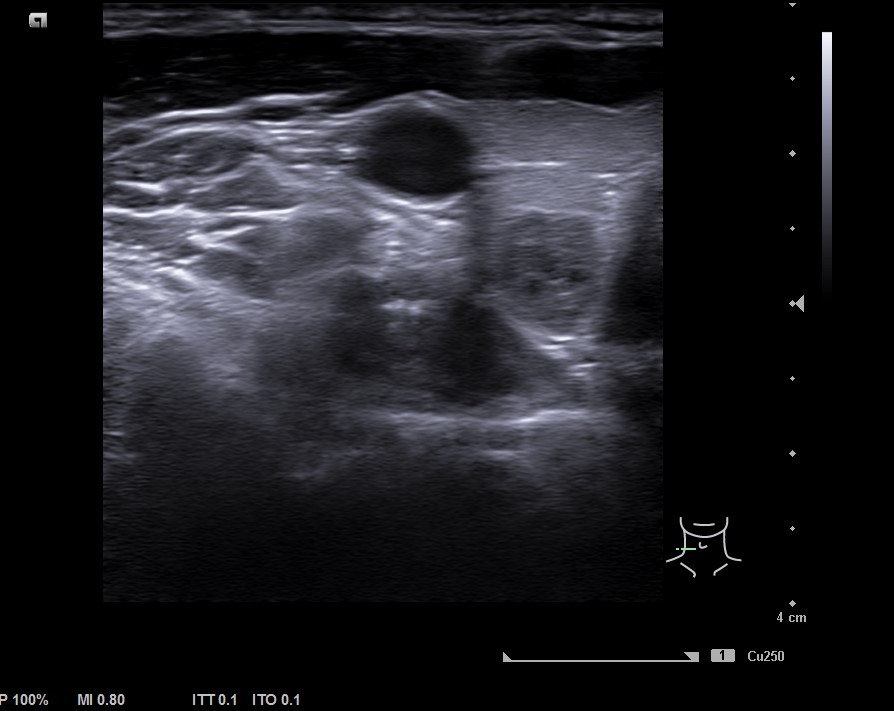

Lóbulo derecho de ecoestrucutra normal. Presenta nódulos hipoecogénicos, pero de características espongiformes y vascularización periférica en situación posteroinferior de 7,5 mm de diámetro, bien definido. TIRADS 2.